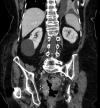

Results: Five patients (2 male, age 44-89 years) were included. Four patients had postoperative PFCs, and 1 presented with a pelvic abscess complicating acute diverticulitis. Two of 5 had fecal diversion; the remaining 3 had unaltered large-bowel anatomy. One case had a concomitant abdominal collection, treated with percutaneous drainage in the same session. An electrocautery-enhanced LAMS delivery system (15 × 10 mm) was used in all cases. EUS-TRD was performed with the direct-puncture technique and lasted less than 10 minutes in 4 cases; in the remaining case, needle puncture and LAMS placement over a guidewire was required, and the procedure length was 14 minutes. The clinical success rate was 100%. LAMSs were removed after a median of 14 (range, 12-24) days. One patient reported partial proximal LAMS migration after 24 days (mild adverse event). No PFC recurrence was observed.